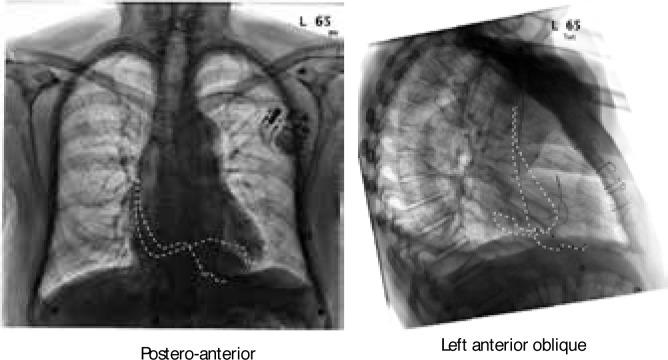

Radial Multi-Site, Longitudinal Multi-Polar Epicardial Left Ventricular Pacing In Tricuspid Valve Disease.

Radial Multi-Site, Longitudinal Multi-Polar Epicardial Left Ventricular Pacing In Tricuspid Valve Disease.三尖瓣疾病中的径向多部位、纵向多极心外膜左心室起搏